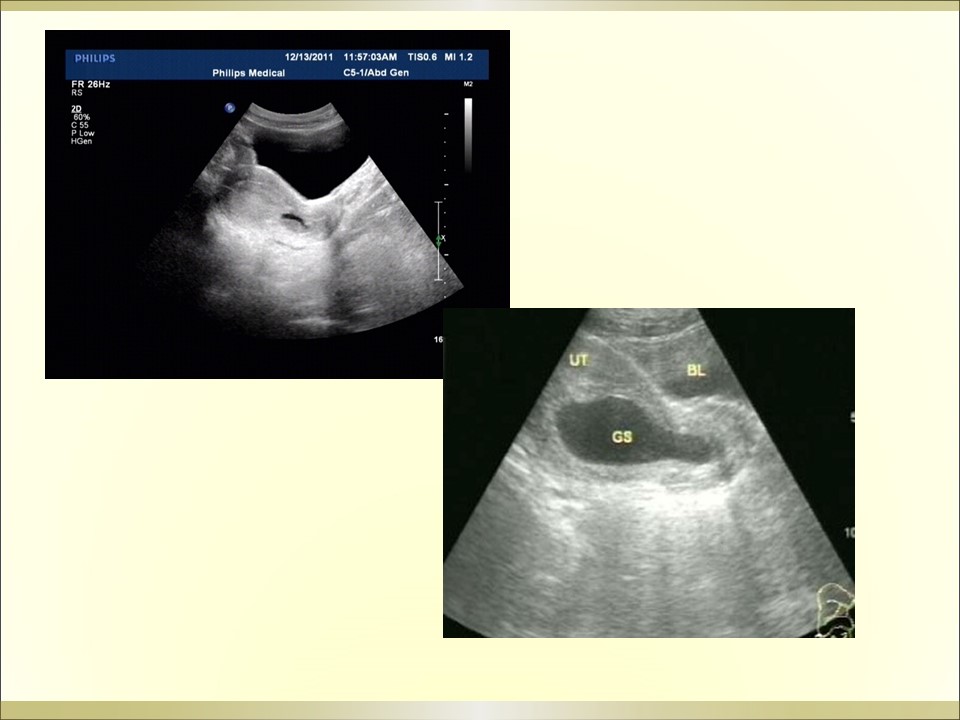

妇产科急腹症是指因妇科疾病引起的剧烈的急性腹痛,可以是原有疼痛突然加剧,或原无疼痛突然发生,是病因较多的常见病,特点是发病急、病变进展快、病情重,需要及时作出病因诊断及治疗。